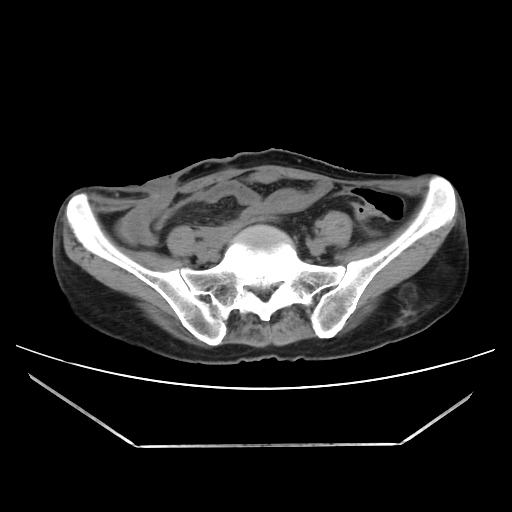

Radiological images:

CT-Scan investigation done on 16Apr16